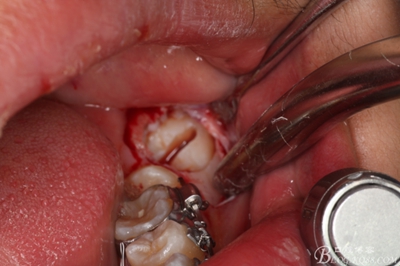

圖3.術(shù)前左側(cè)下頜口內(nèi)照片:37近中阻生,38口內(nèi)看不到。